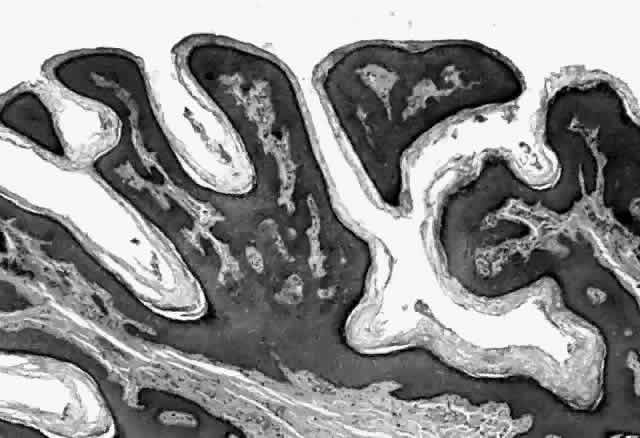

HPV-induced conjunctival squamous papillomas demonstrate papillomatosis, acanthosis, and koilocytosis (Fig. 6). Because they are mucous membrane lesions, those of the conjunctiva and lacrimal sac show no granular cell layer but will show keratinization if they are large or exposed (Fig. 7). In our experience the frequency of koilocytes is variable, even in lesions almost certain to be viral (Fig. 8). Scattered inflammatory cells may be present in the cores or epithelium. Virus can be detected immunohistochemically in the nuclei of the cells (Fig. 9).

Early dysplastic lesions (conjunctival intraepithelial neoplasia) show thickened epithelium with extension of basal-like cells beyond the basal layer, but cells continue to mature into flat squamous cells. Mitoses are also seen higher in the epithelium. As the degree of dysplasia worsens, the more superficial epithelium is replaced at higher levels by basal-type cells, mitoses can be seen further from the basal layer, and atypia of cells becomes more pronounced. With squamous cell carcinoma in situ, there is full-thickness dysplasia, cellular atypia is variable, and mitoses can be seen at all layers of the epithelium. Invasive squamous cell carcinomas are usually well differentiated. Pleomorphism, hyperchromaticity, dyskeratosis, and horn pearls are seen. Epithelial cell clusters can be seen invading below the basement membrane. Inflammatory cells are common in the substantia propria.